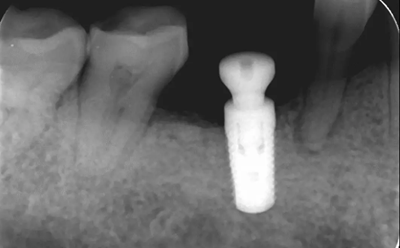

16、修復(fù)前根尖片

二期術(shù)后1月根尖顯示種植體周圍骨質(zhì)穩(wěn)定,無進(jìn)一步吸收。

(2018年5月25日)